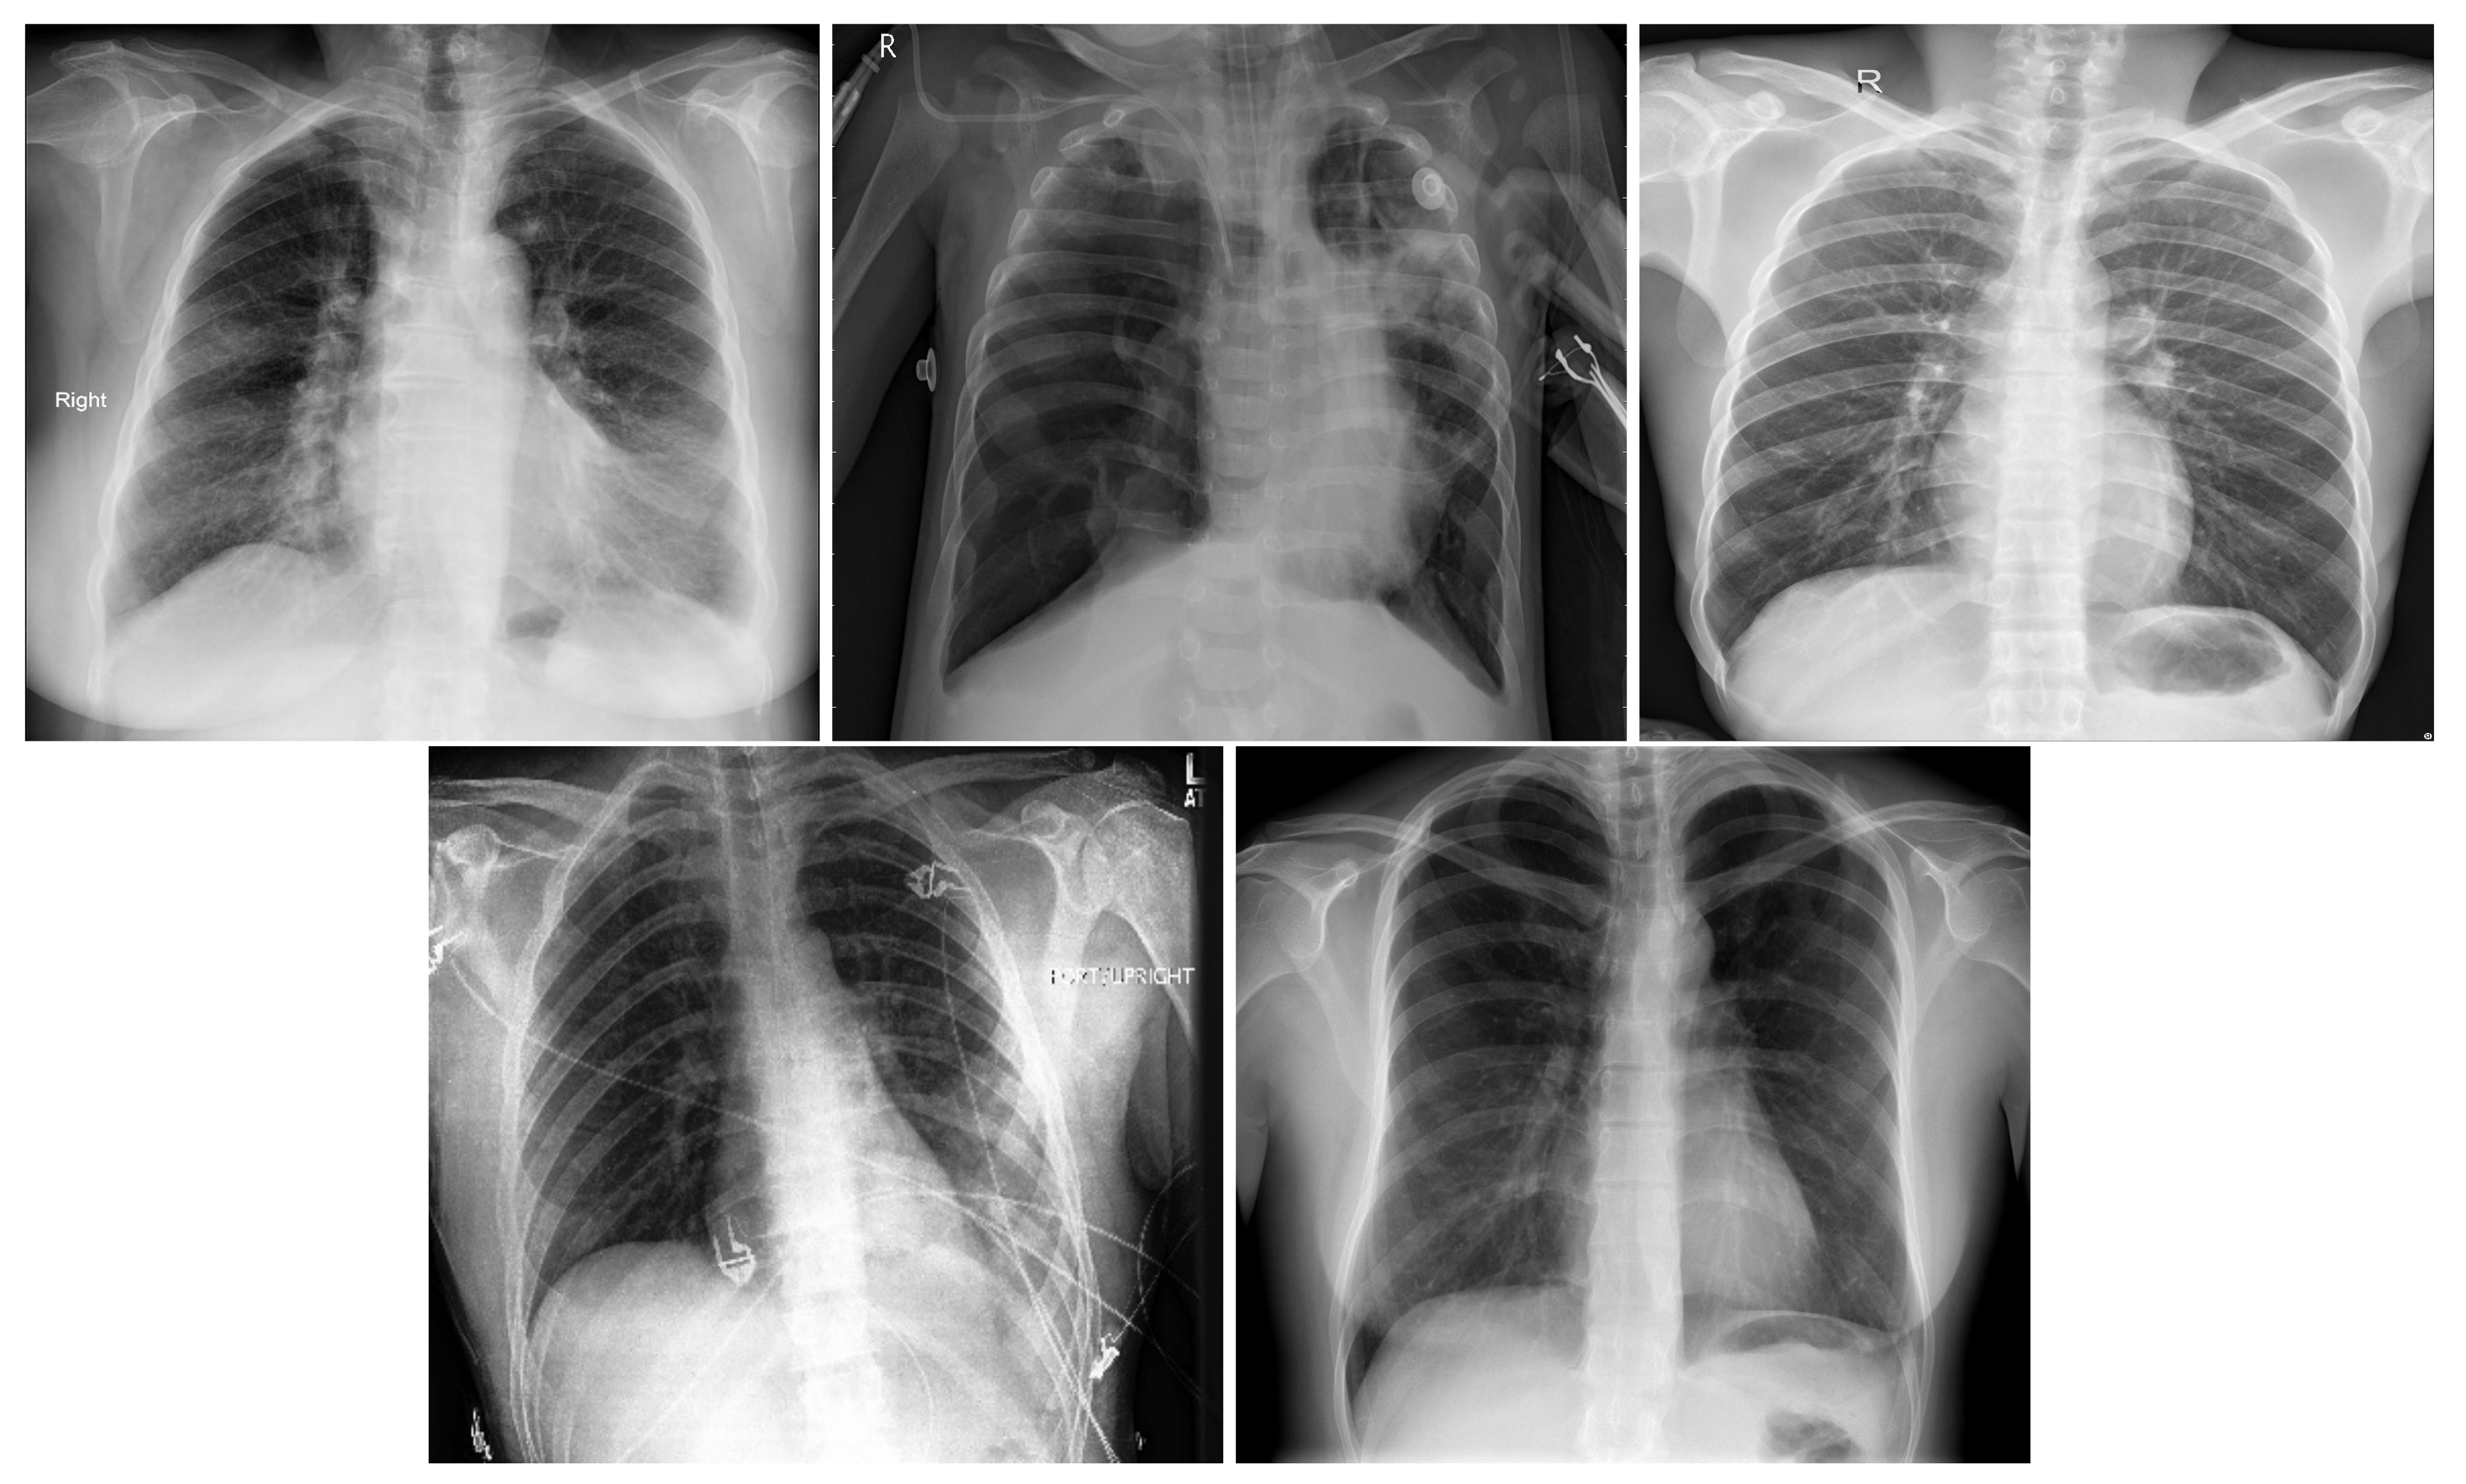

Table 2 summarizes the three-class database number of images by split and their resources. Figure 1 shows an X-ray example for each class of the three-class COVID-19 database.

Figure 1. Samples from the three-class Covid-19 database: Covid-19 (left), Pneumonia (center), and Normal (right).